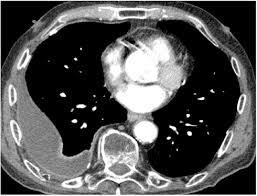

Ultrasound findings are relevant for pleural infection as in heavily septated or loculated effusions, the biochemical results can be different in the discrete areas, so can give falsely reassuring results. Malignant pleural effusion, lymphangitis carcinomatosa: In patients with symptomatic malignant pleural effusions with nonexpandable lung, failed pleurodesis, or loculated effusion, we suggest the use of ipcs over chemical pleurodesis. Rather than layering laterally and blunting of the costophrenic angle, the pleural fluid lies almost exclusively betw. Nov 28, 2018 · pericardial fluid drainage can be performed by percutaneous catheter drainage or open surgical approach. The parietal pericardium (arrow) clearly separates the loculated pericardial effusion (∗) from the pleural effusion (p). 34 the fluid may accumulate due to overproduction from diseased pleura, obstruction of lymphatic channels, or atelectasis of adjacent lung. 30 effusions are also sometimes referred to as sonographically complex, which is an echogenic effusion with or without septations. The precise pathophysiology of fluid accumulation varies according to underlying aetiologies. R hydropneumothorax, r pleura mass (mpm), mesotheliomaasbestos: Individual patient characteristics (eg, loculated vs circumferential, recurrent pericardial effusion, need for pericardial biopsy and location of pericardial effusion) and local practice patterns aid in deciding the optimal method of drainage. Help for veterans · speak to a doctor · free book on mesothelioma Pleural effusions are a common medical problem with more than 50 recognised causes including disease local to the pleura or underlying lung, systemic conditions, organ dysfunction and drugs.1 pleural effusions occur as a result of increased fluid formation and/or reduced fluid resorption.

Help for veterans · speak to a doctor · free book on mesothelioma Posterior effusion, loculated, empyema, ultrasound, parapneumonic effusion, streptococcus milleri: R hydropneumothorax, r pleura mass (mpm), mesotheliomaasbestos: Ultrasound findings are relevant for pleural infection as in heavily septated or loculated effusions, the biochemical results can be different in the discrete areas, so can give falsely reassuring results. Help for veterans · speak to a doctor · free book on mesothelioma Nov 28, 2018 · pericardial fluid drainage can be performed by percutaneous catheter drainage or open surgical approach. Malignant pleural effusion, lymphangitis carcinomatosa: Learn about the symptoms & causes of pleural effusions and pleural mesothelioma. Pleural effusions are a common medical problem with more than 50 recognised causes including disease local to the pleura or underlying lung, systemic conditions, organ dysfunction and drugs.1 pleural effusions occur as a result of increased fluid formation and/or reduced fluid resorption. The precise pathophysiology of fluid accumulation varies according to underlying aetiologies. In patients with symptomatic malignant pleural effusions with nonexpandable lung, failed pleurodesis, or loculated effusion, we suggest the use of ipcs over chemical pleurodesis. The parietal pericardium (arrow) clearly separates the loculated pericardial effusion (∗) from the pleural effusion (p). Subpulmonic effusions (also known as subpulmonary effusions) are pleural effusions that can be seen only on an erect projection.